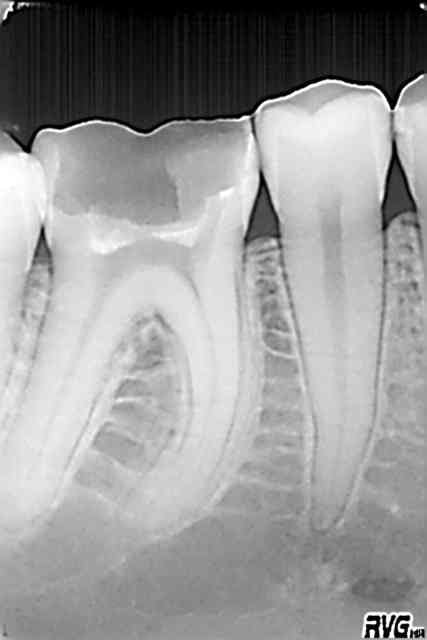

Pour compléter le cas Katia. Je l'ai vue en 2002 pour la première fois (status). N'a pas donné suite aux soins (simples) à l'époque. Revue en urgence en 2003 pour endo de 46.

"Fidélisée" ailleurs et revue en fin 2013 dans l'état que vous connaissez.

Note : elle a l'air mieux sous subutex car elle vient à ses rendez vous. Alors oui ca vaut le coup de faire un petit quelque chose fusse au tarif CMU.

T'es pas a l'apex tu vaux rien :p

J'étais nul en endo en 2002.))))